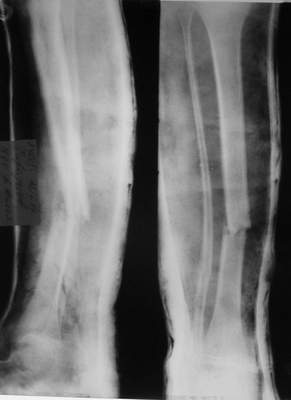

A> Так как речь зашла непосредственно о травме, см этапные

A> снимки. Как все было

Вопросов нет.

Встречаются и при переломах голени (б/б с вальгусным смещением).

A> Тем более с такой дугой

См. аттачт.

A> и на этом

A> уровне.

К сожалению, в своем компьютере я таких случаев не нашел, но раза 2 встречал.